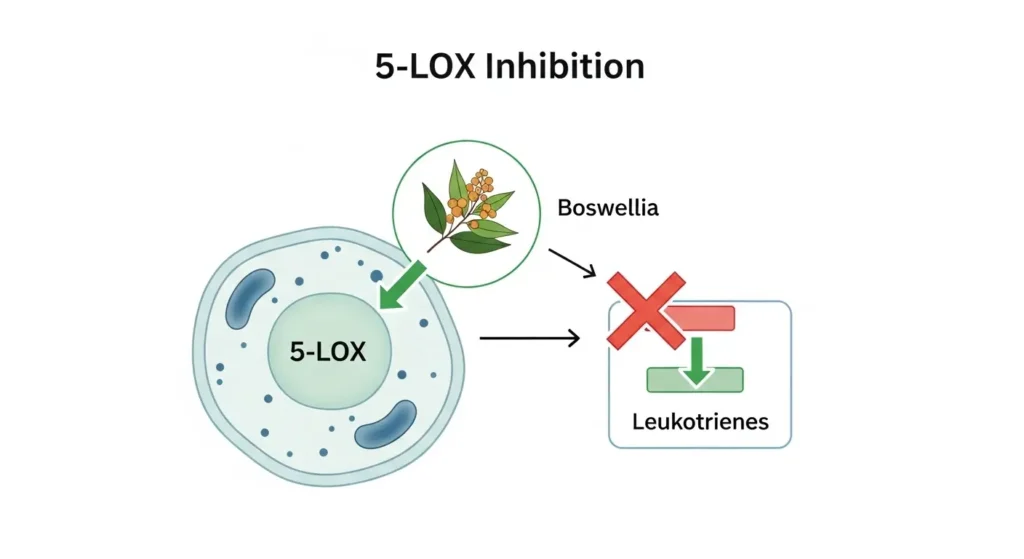

3. Powerful Anti-Inflammatory Effects

Unique Mechanism:

Boswellia’s anti-inflammatory action differs from other herbs and NSAIDs, making it particularly valuable.

How Boswellia Works Differently:

✅ 5-LOX Inhibition (Primary):

- Blocks 5-lipoxygenase enzyme

- Prevents leukotriene synthesis (powerful inflammatory molecules)

- Different pathway than COX inhibitors (NSAIDs)

- No gastric side effects like NSAIDs

✅ Does NOT Inhibit COX:

- Unlike NSAIDs that block COX-1 and COX-2

- Preserves protective prostaglandins in stomach

- Better gastrointestinal safety profile

- Can be combined with other anti-inflammatories

✅ Additional Anti-Inflammatory Actions:

- Reduces NF-κB activation (inflammatory gene expression)

- Inhibits pro-inflammatory cytokines

- Protects against oxidative stress

- Reduces tissue inflammation markers

Clinical Results:

- Reduces inflammatory markers (CRP, ESR) by 20-40%

- Decreases white blood cell infiltration in inflamed tissues

- Provides sustained anti-inflammatory effects

Study in Planta Medica confirms boswellia’s unique 5-LOX inhibition mechanism.